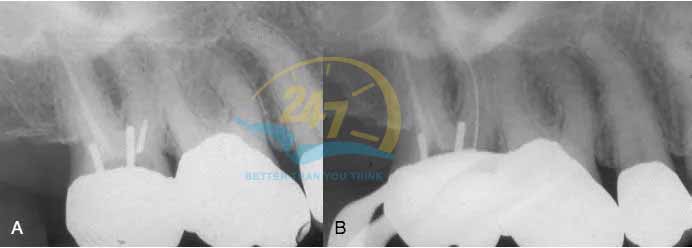

Vì tình trạng gãy trâm nội nha là sự cố xảy ra khá phổ biến trong điều trị nha khoa nên phương án xử lý trâm bị gãy luôn là vấn đề được quan tâm hàng đầu. Thực tế hiện nay cho thấy, có rất nhiều hệ thống, dụng cụ và cách để lấy trâm gãy. Tuy nhiên, khả năng thành công còn phụ thuộc vào vị trí của đoạn gãy trong ống tủy và đặc điểm ống tủy. Cụ thể:

- Nếu trâm gãy ở 1/3 cổ thì bác sĩ sẽ cẩn thận để lấy phần trâm gãy ra ngoài.

- Nếu trâm gãy ở 1/3 giữa và trên đoạn cong, bác sĩ cần phải lách qua hoặc cố gắng lấy ra ngoài.

- Nếu trâm gãy ở 1/3 chóp và đoạn dưới cong của ống tủy thì bác sĩ cần cố gắng lách qua.